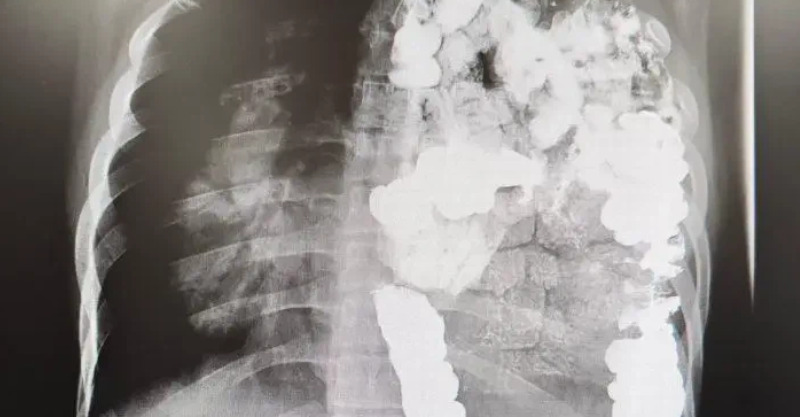

根據《TVBS新聞網》報導,醫師鍾孟軒近日在節目《醫師好辣》分享過去的醫療文獻,一位器官捐贈者在往生後捐出器官,造福多位等待移植的病患。不料,短短2到3年內,所有接受器官移植的患者竟然全數罹患乳癌,更令人震驚的是,就連男性受贈者也未能倖免!

醫療團隊經過深入調查,透過基因比對分析,終於發現這些癌症的共同源頭:「他們發現,喔,原來是從那個大愛捐贈者那裡而來的乳癌」」原來當初在進行器官捐贈時,捐贈者體內就已經存在「未被發現」的乳癌。